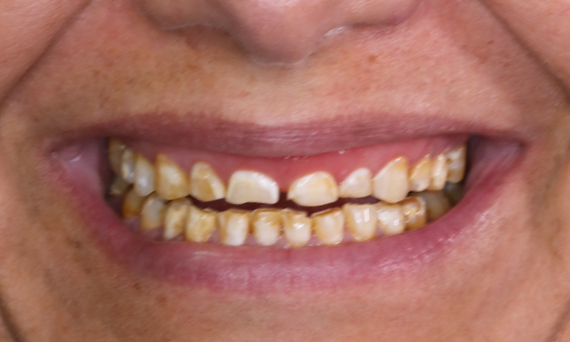

Before: Patient, dissatisfied with her smile due to tooth discoloration.

After: Ten highly aesthetic single crowns, individualised with stains.